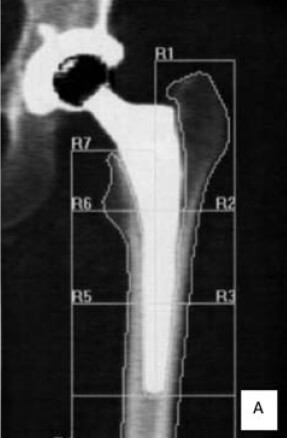

Los defectos alrededor de los implantes son difíciles de detectar de manera precoz y la cantidad de pérdida ósea, no es estimada, sino hasta muy tarde en estudios radiológicos, para algunos cuando ya existe un déficit de más del 30%. La importancia de la DXA es para evaluar el incremento del remodelado óseo y la capacidad de osteointegración en los alrededores de implantes intra o extra medulares, cuyas mediciones se deben realizar antes de la colocación del implante para valorar la calidad del hueso y después para controlar los cambios en la vecindad del tejido implantado o en los huesos distales afectados por cambios en la disposición de la carga de peso. La DXA para evaluar el aflojamiento peri protésico ha sido utilizada desde 1993 y cada día se evidencian más reportes de su utilidad para valorar los componentes acetabular, vástago y los de las prótesis de rodilla. En el caso particular de la cadera se cuenta con un software procedente del estudio de Gruen, que divide el fémur proximal en siete(7) zonas. Diversos estudios clínicos reportan con esta metodología la evolución a los 3, 5 y 10 años con diferentes diseños de prótesis y de su cubrimiento. Mejoras en el software y en la tecnología han hecho de la DXA un instrumento válido para proporcionar una medida adecuada de la DMO peri protésica y su osteointegracion (ver Figura N° 2) (22-26).

Figura Nº 2.

Determinación por DXA de la osteointegración de una artroplastia total de cadera. En la figura A las siete zonas de Gruen y en la B las tres medidas tomadas a nivel del acetábulo de acuerdo al protocolo de Mérida. Cortesía del Instituto de Osteoporosis y Densitometría Ósea (Mérida. Venezuela)

En este momento, la DXA, se considera un método útil para evaluar la redistribución de las fuerzas mecánicas alrededor de la cadera luego del implante y la remodelación alrededor del vástago, independientemente de la geometría y el cubrimiento. La mayoría de los estudios con DXA han carecido de seguimiento de más de 5 años, y muchos han utilizado el fémur opuesto como el control en el momento de la investigación. Tres años después de la artroplastia se pierde el 40% del contenido mineral óseo promedio en el trocánter menor (zona 7), y 28% en las zonas 5 y 6 de la corteza medial. A los 14 años, después de la operación se había perdido el 40% de hueso proximal y 49% distal. Los datos sugieren que la progresión es mayor hacia distal y medial(27, 28).

De esta manera la DXA es útil porque permite la cuantificación, en etapas tempranas, de la perdida de hueso alrededor del implante. En varios estudios, las alteraciones de la corteza de la zona medial femoral (Zona 7) se mantienen y se agravan con el tiempo. Este cambio áreal alterará las mediciones de densidad ósea. Tal y como se muestra en la tabla de trabajo realizado a 24 pacientes del IAHULA de Mérida, Venezuela luego de colocarle artroplastia no cementada en la cadera, las zonas más afectadas eran la 4 y la 7 (ver Cuadro N°1)(29).